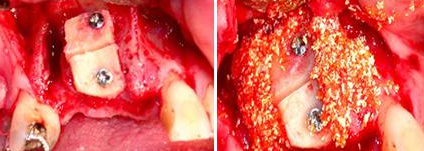

Situação que o paciente se apresentou no consultório para colocação de implantes e restabelecimento da estética e função dos dentes. Como o tecido ósseo havia sido reabsorvido, para a realização dos implantes, enxerto de ósseo e plasma rico em plaquetas (PRP) teve que ser realizado. Na fotografia vemos os parafusos, fixando os blocos de osso que colocados, e recobertos com PRP (Fotos).

Nestas fotografias estão: O PRP utilizado junto com o enxerto de osso e os implantes colocados 6 meses após a cirurgia.

A primeira fotografia mostra o caso após a colocação das coroas provisórias sem a gengiva artificial de resina (epítese). Na segunda fotografia o caso concluído e a gengiva artificial colocada, mostrando a recuperação ideal possível da estética do paciente. Importante salientar a satisfação e importância desses procedimentos para o paciente, que havia se submetido a esse longo tratamento.